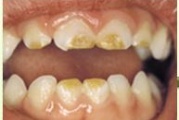

Tetratsükliini liigtarbimise tõttu värvunud hambad

Hammaste defektid